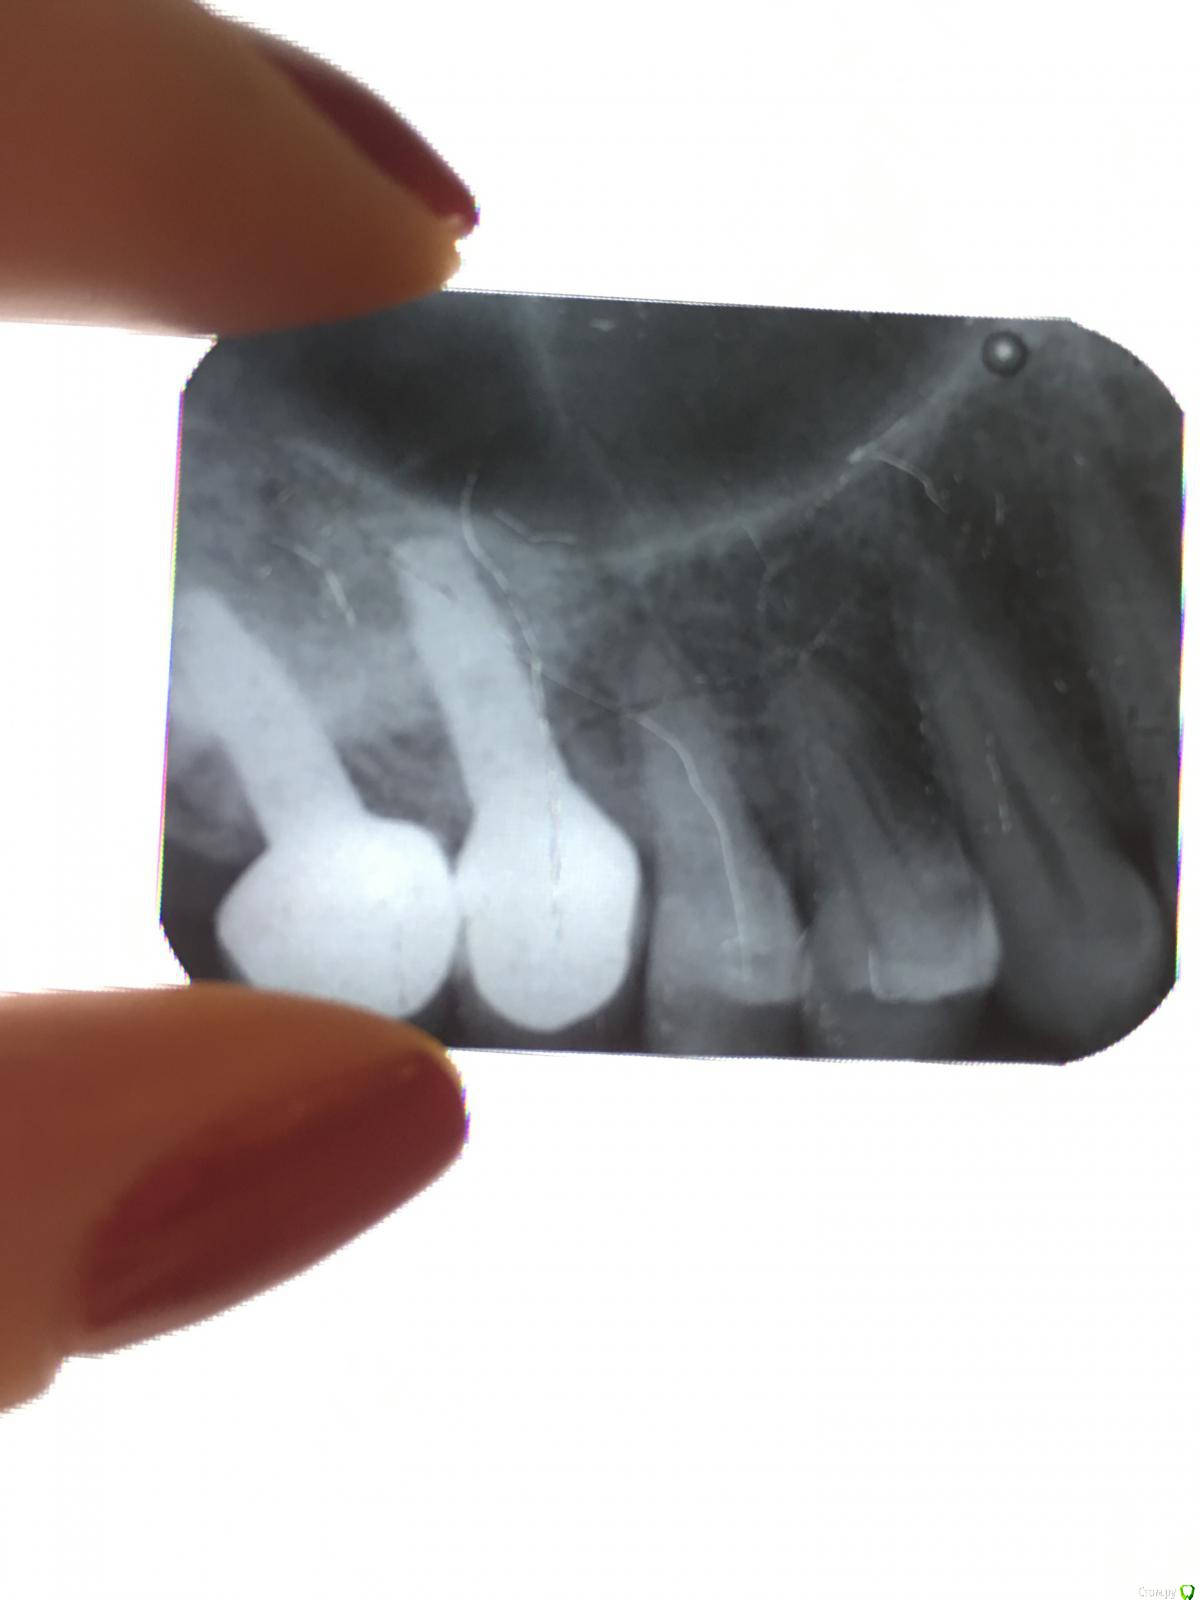

Ольгаxxx Опубликовано 28 ноября, 2019 Автор Поделиться Опубликовано 28 ноября, 2019 (изменено) Здравствуйте. Подскажите, пожалуйста, какие мои действия должны быть дальше? Пришла к стоматологу на лечение кариеса в 4ке. (см. пост выше). Врач посмотрев меня, сказал, что не видит там кариеса. Но реакция на сладкое у меня присутствует, не всегда, но она есть! Посмотрите, пожалуйста, фото сделанные мной, неужели там нет кариеса? И это второй врач, на минуточку, говорит, что не видит кариеса и в целом все ок. Как так то? Может заново прицельный сделать? Спасибо, если ответите. Изменено 28 ноября, 2019 пользователем Ольгаxxx Ссылка на комментарий

red_butler Опубликовано 28 ноября, 2019 Поделиться Опубликовано 28 ноября, 2019 Может заново прицельный сделать? сделайте.Также можно найти клинику где есть http://forum.stom.ru/topic/39327-kavo-diagnocam-diagnokam/ Ссылка на комментарий

Ольгаxxx Опубликовано 28 ноября, 2019 Автор Поделиться Опубликовано 28 ноября, 2019 сделайте.Также можно найти клинику где есть http://forum.stom.ru/topic/39327-kavo-diagnocam-diagnokam/Я правильно понимаю, это экран с увеличением и типа лупой на ручке? Если да, то будете удивленны, меня один из стоматологов смотрелс помощью этого прибора. Но я больше указывала на 5ку, а сейчас чувствую, что все-таки в 4ке локализация от сладкого идет. И он сказал в 4ке не видит кариеса(((. А по фото, что Вы скажите? Ссылка на комментарий

red_butler Опубликовано 28 ноября, 2019 Поделиться Опубликовано 28 ноября, 2019 Я правильно понимаю, это экран с увеличением и типа лупой на ручке? Если да, то будете удивленны, меня один из стоматологов смотрелс помощью этого прибора. Но я больше указывала на 5ку, а сейчас чувствую, что все-таки в 4ке локализация от сладкого идет. И он сказал в 4ке не видит кариеса(((. А по фото, что Вы скажите?Нет, это не фонарик. На фото явного кариеса не вижу Ссылка на комментарий